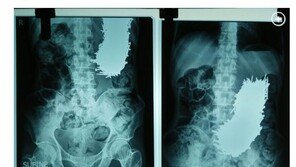

극심한 복통 호소한 男, X레이 찍으니 뾰족한 쇠못 600여 개가…

극심한 복통을 호소한 40대 인도 남성의 배 속에서 뾰족한 쇠못 600여 개가 발견됐다. 지난달 31일(이하 현지시간) 영국 미러, 미국 뉴욕포스트 등 외신들은 인도에 거주하는 남성 프라딥 쿠마르 달리(48)가 최근 한 병원에서 배 속에 있는 쇠못 600여 개를 제거하는 수술을 받…